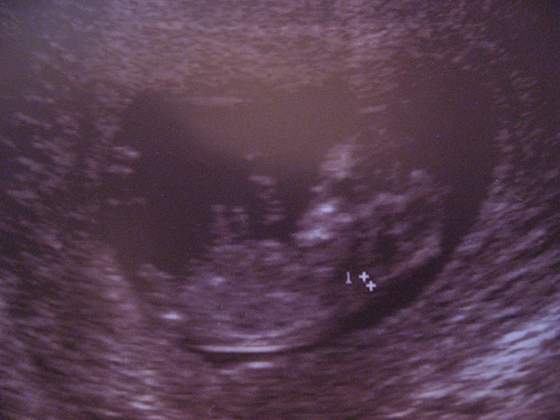

o korka tez juz pokazny

to twoja dzidzia ma tyle samo milimetrow co moja na usg i ja tez sie martwie ze moja za malutka jest jak na temn tydzien i juz sie zastanawialam czy to moze dlatego ze teraz w ciazy niejem duzo ...ale niema sie co martwic wazne ze zywa i zdrowa :-)A to moja Kruszynka z 1 dnia 13 tyg.(wg. USG) choc dla mnie jest troszke za malutka na ten tydz. Ma 49,5mm. Z OM termin mi wychodzi na 17 stycznia a z USG na 12 stycznia. Wszystko u niej jest w porzadju, przezierność i kości czaszki ok. Także jestem szczęśliwa.

Zobacz załącznik 261780

to twoja dzidzia ma tyle samo milimetrow co moja na usg i ja tez sie martwie ze moja za malutka jest jak na temn tydzien i juz sie zastanawialam czy to moze dlatego ze teraz w ciazy niejem duzo ...ale niema sie co martwic wazne ze zywa i zdrowa :-)